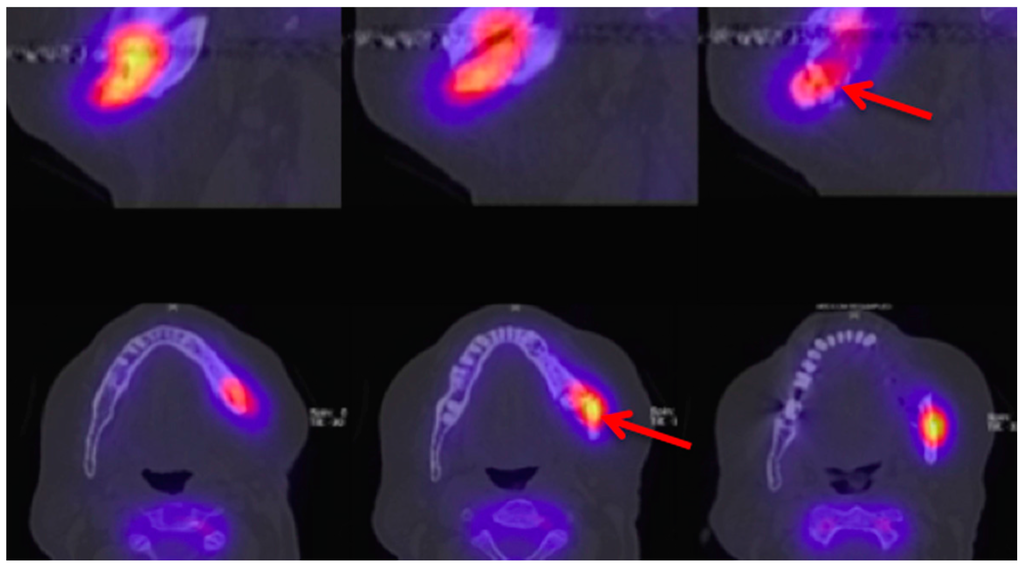

Figure 9.

Technetium-99m-3,3-diphosphono-1,2-propanodicarboxylicacid (99Tcm-DPD) SPECT/CT (Siemens, Symbia) Patient: 66 years old, male, secondary osteoporosis due to castration, alendronate. First row sagittal, second row axial view; 4.5 h after injection (bone phase). The uptake in the left mandible is clearly visible (red arrow). For the panoramic radiograph see Figure 3. AAMOS staging: stage 3.

Information from a planar scintigraphy is displayed in a two-dimensional form in contrast to SPECT. An example of technetium-99m-3,3-diphosphono-1,2-propanodicarboxylicacid (99Tcm-DPD) SPECT and 99Tcm-DPD SPECT/CT is seen in Figure 8 and Figure 9 respectively.

In SPECT imaging, the distribution of the radionuclide is monitored in multiple two-dimensional images and from multiple angles. From these datasets, a three-dimensional image is then calculated. If anatomical imaging should be added, hybrid SPECT/CT scanners are available. For detecting bony infections, technetium-99m methylene diphosphonate (99Tcm-MDP) or technetium-99 m-DPD (99Tcm-DPD) are frequently used nuclides; they show no significant differences in detecting “pathologically increased bone uptake” [47]. MRONJ should not show an uptake in the necrotic zone, but due to the associated infection, a nuclide uptake may be seen. O’Ryan et al. [48] published a retrospective study on MRONJ patients who had received whole-body planar bone scintigraphy. They used the following scoring system for the jaw: “score 0, no visual evidence of increased uptake was present; score 1, uptake was mild and equal to that in the sternum; and score 2, uptake was intense and greater than that in the sternum” [48]. The comparison with the sternum uptake was based on a paper published by Kakhki et al. [49]. Kakhki et al.’s paper, a study on 334 patients who had no diseases of the sternum/chest wall or malignancy, assessed the normal uptake in a sternum considering the age of the patient [49]. O’Ryan et al. found a nuclide uptake in 65.7% of their MRONJ patients. From their point of view, scintigraphy might have a prognostic value and physicians should watch out for newly occurring uptake in the jaws [48]. Thomas et al. assessed the impact of bone scintigraphy in patients with metastatic castration-resistant prostate cancer who had received bisphosphonates. Their focus was on early prediction of clinically asymptomatic MRONJ. MRONJ was significantly more often developed in patients with a pathological tracer uptake [50]. Ristow et al. investigated the bone turnover in the jaw of breast cancer patients who had received no antiresorptive medication, bisphosphonates, or denosumab. Interestingly, they found that “there was similar turnover of bone in the mandible compared with other skeletal sites (such as the femur), while the maxilla showed significantly higher turnover”. Since the majority of MRONJ lesions occur in the mandible, the bone turnover role of the MRONJ pathogenesis must be further reviewed [51].